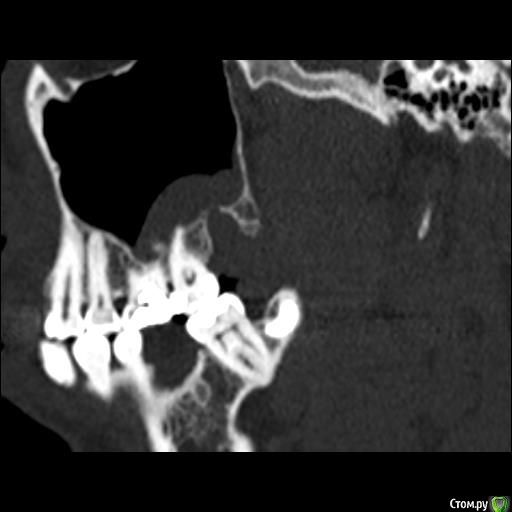

Юлия2386 Опубликовано 30 июля, 2020 Поделиться Опубликовано 30 июля, 2020 Добрый день, уважаемые врачи! Прошу вашей помощи, так как уже замучалась я конкретно. У меня уже 9 месяцев боли в правой стороне лица давящего характера. Давит на лоб, глаз, иногда висок. С декабря 2019 выявили фронтит-гайморит, проходила лечение у Лора и ещё невролога. Окончательного результата по выздоровлению за это время не достигнуто. Видимо это одномерный гайморит, так как постоянно какое-то воспаление формировалось у зубов 1.6;1.7;1.8. Многие стоматологи не видят проблем в зубе 1.6. Посоветовали удалить зуб 1.8 так как там был глубокий десневого карман. Удалила, а воспаление разрослось ещё больше (после удаления поцарапала щеку зубом 1.7, возможно из-за этого разрослось воспаление?!) После удаления прошёл месяц, а картина сейчас такая https://yadi.sk/d/ziceEN_jVZ9IkwВ итоге последний врач сказал, что все-таки проблема идёт от зуба 1.6, так как не запломбирован один канал, но из-за того что у зуба входят корни в гайморовых пазуху, лечить его не видет смысла, порекомендовал его удалить и через лунку вычиститься всю слизь, но он этим не занимается. Теперь я замешательстве и не знаю, что мне с этим делать, а самое ужасное, что глаз от этого болит( Уважаемые доктора, очень прошу вашей помощи, выскажите пожалуйста ваше мнение и может посоветуете к кому с этим можно обратиться в Москве. Ссылка на комментарий

wladdX Опубликовано 31 июля, 2020 Поделиться Опубликовано 31 июля, 2020 Представленная спиральная КТ не позволяет детально рассмотреть корневые каналы зубов и тп, чтобы получить какое-то внятное суждение.На уровне зубов 18, 17 и 16 есть локальное утолщение слизистой оболочки синуса и это всё, что из этого исследования можно выяснить. Адекватность обтурации корневых каналов зуба 16 оценить не представляется возможным (по крайней мере в моём понимании).Я бы порекомендовал сделать КЛКТ (конусно-лучевую компьютерную томографию), используемую в стоматологии. Ссылка на комментарий